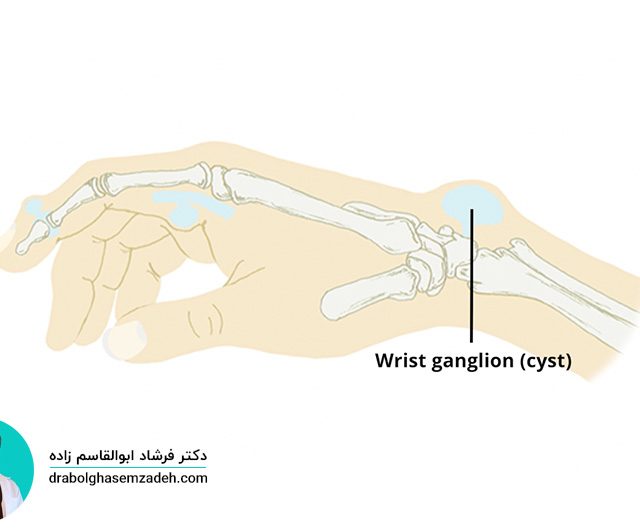

یکی از بیماری های مفصلی پا علائم شدید و ناگهانی به همراه دارد، بیماری نقرس است. عوامل متعددی باعث افزایش این بیماری پیچیده آرتروزی در بیماران به خصوص مردان می شود. به دلیل حملات و درد ناگهانی که بیماری نقرس دارد، تحمل آن می تواند بسیار رنج آور و دردناک باشد. شناخت علائم بیماری نقرس […]...